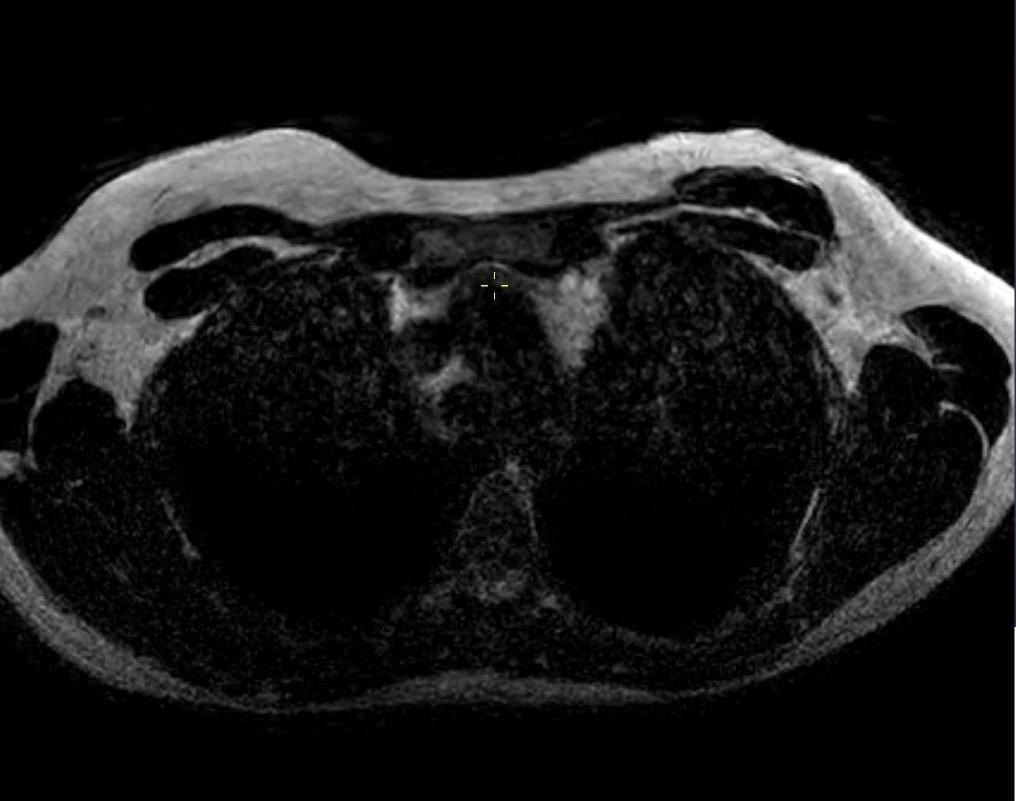

2023年的乳腺MRI检查可以看到双侧全乳重建术后自体脂肪移植(AFT)的效果,其表现为双侧乳晕后异质性肿块。

轴位T1WI图像(图4)及对比增强T1WI脂肪抑制图像(图5)显示,肿块中心见含脂肿块,边缘环绕着薄薄的强化带。